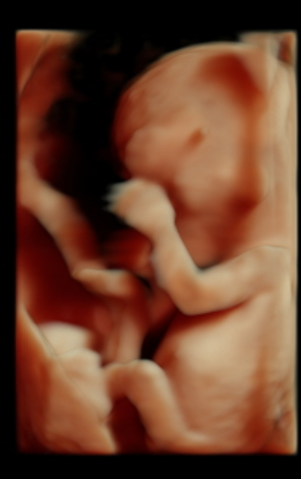

Наш 1 скрининг в 12 недель ♥️

Всё о нашей беременностиНаконец то дождались 1 скрининга, все у нас хорошо)) ттт🙏узистка сказала 70 % что будет девочка, я счастлива, муж сказал что все равно надеется что будет сын) мы ходили вместе, сказал что он успел разглядеть там пипеньку😂все узи крутилась, отварачивалась,закрывала лицо ручками))ну или закрывал))

Спасибо) да это у нас узи студия, там и 3д и обычное узи делают за раз в разных режимах смотрят)) у нас ктр не очень большой 4.9, мы на 2 дня немножко отстаем в размере)